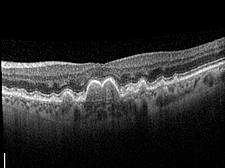

Abb.1:Trockene Makuladegeneration – Schnittbild der Makula mit Ablagerungen in Form von Drusen, die vor allem im Zentrum unter der Stelle des schärfsten Sehens von unten auf die darüber liegende Netzhaut drücken.

Bei der trockenen Makuladegeneration sammeln sich unter der Makula Stoffwechselablagerungen in Form sogenannter Drusen an, welche langsam an Größe und Dicke zunehmen und dadurch die Funktion der lichtempfindlichen Sehzellen immer mehr einschränken (Abb. 1).